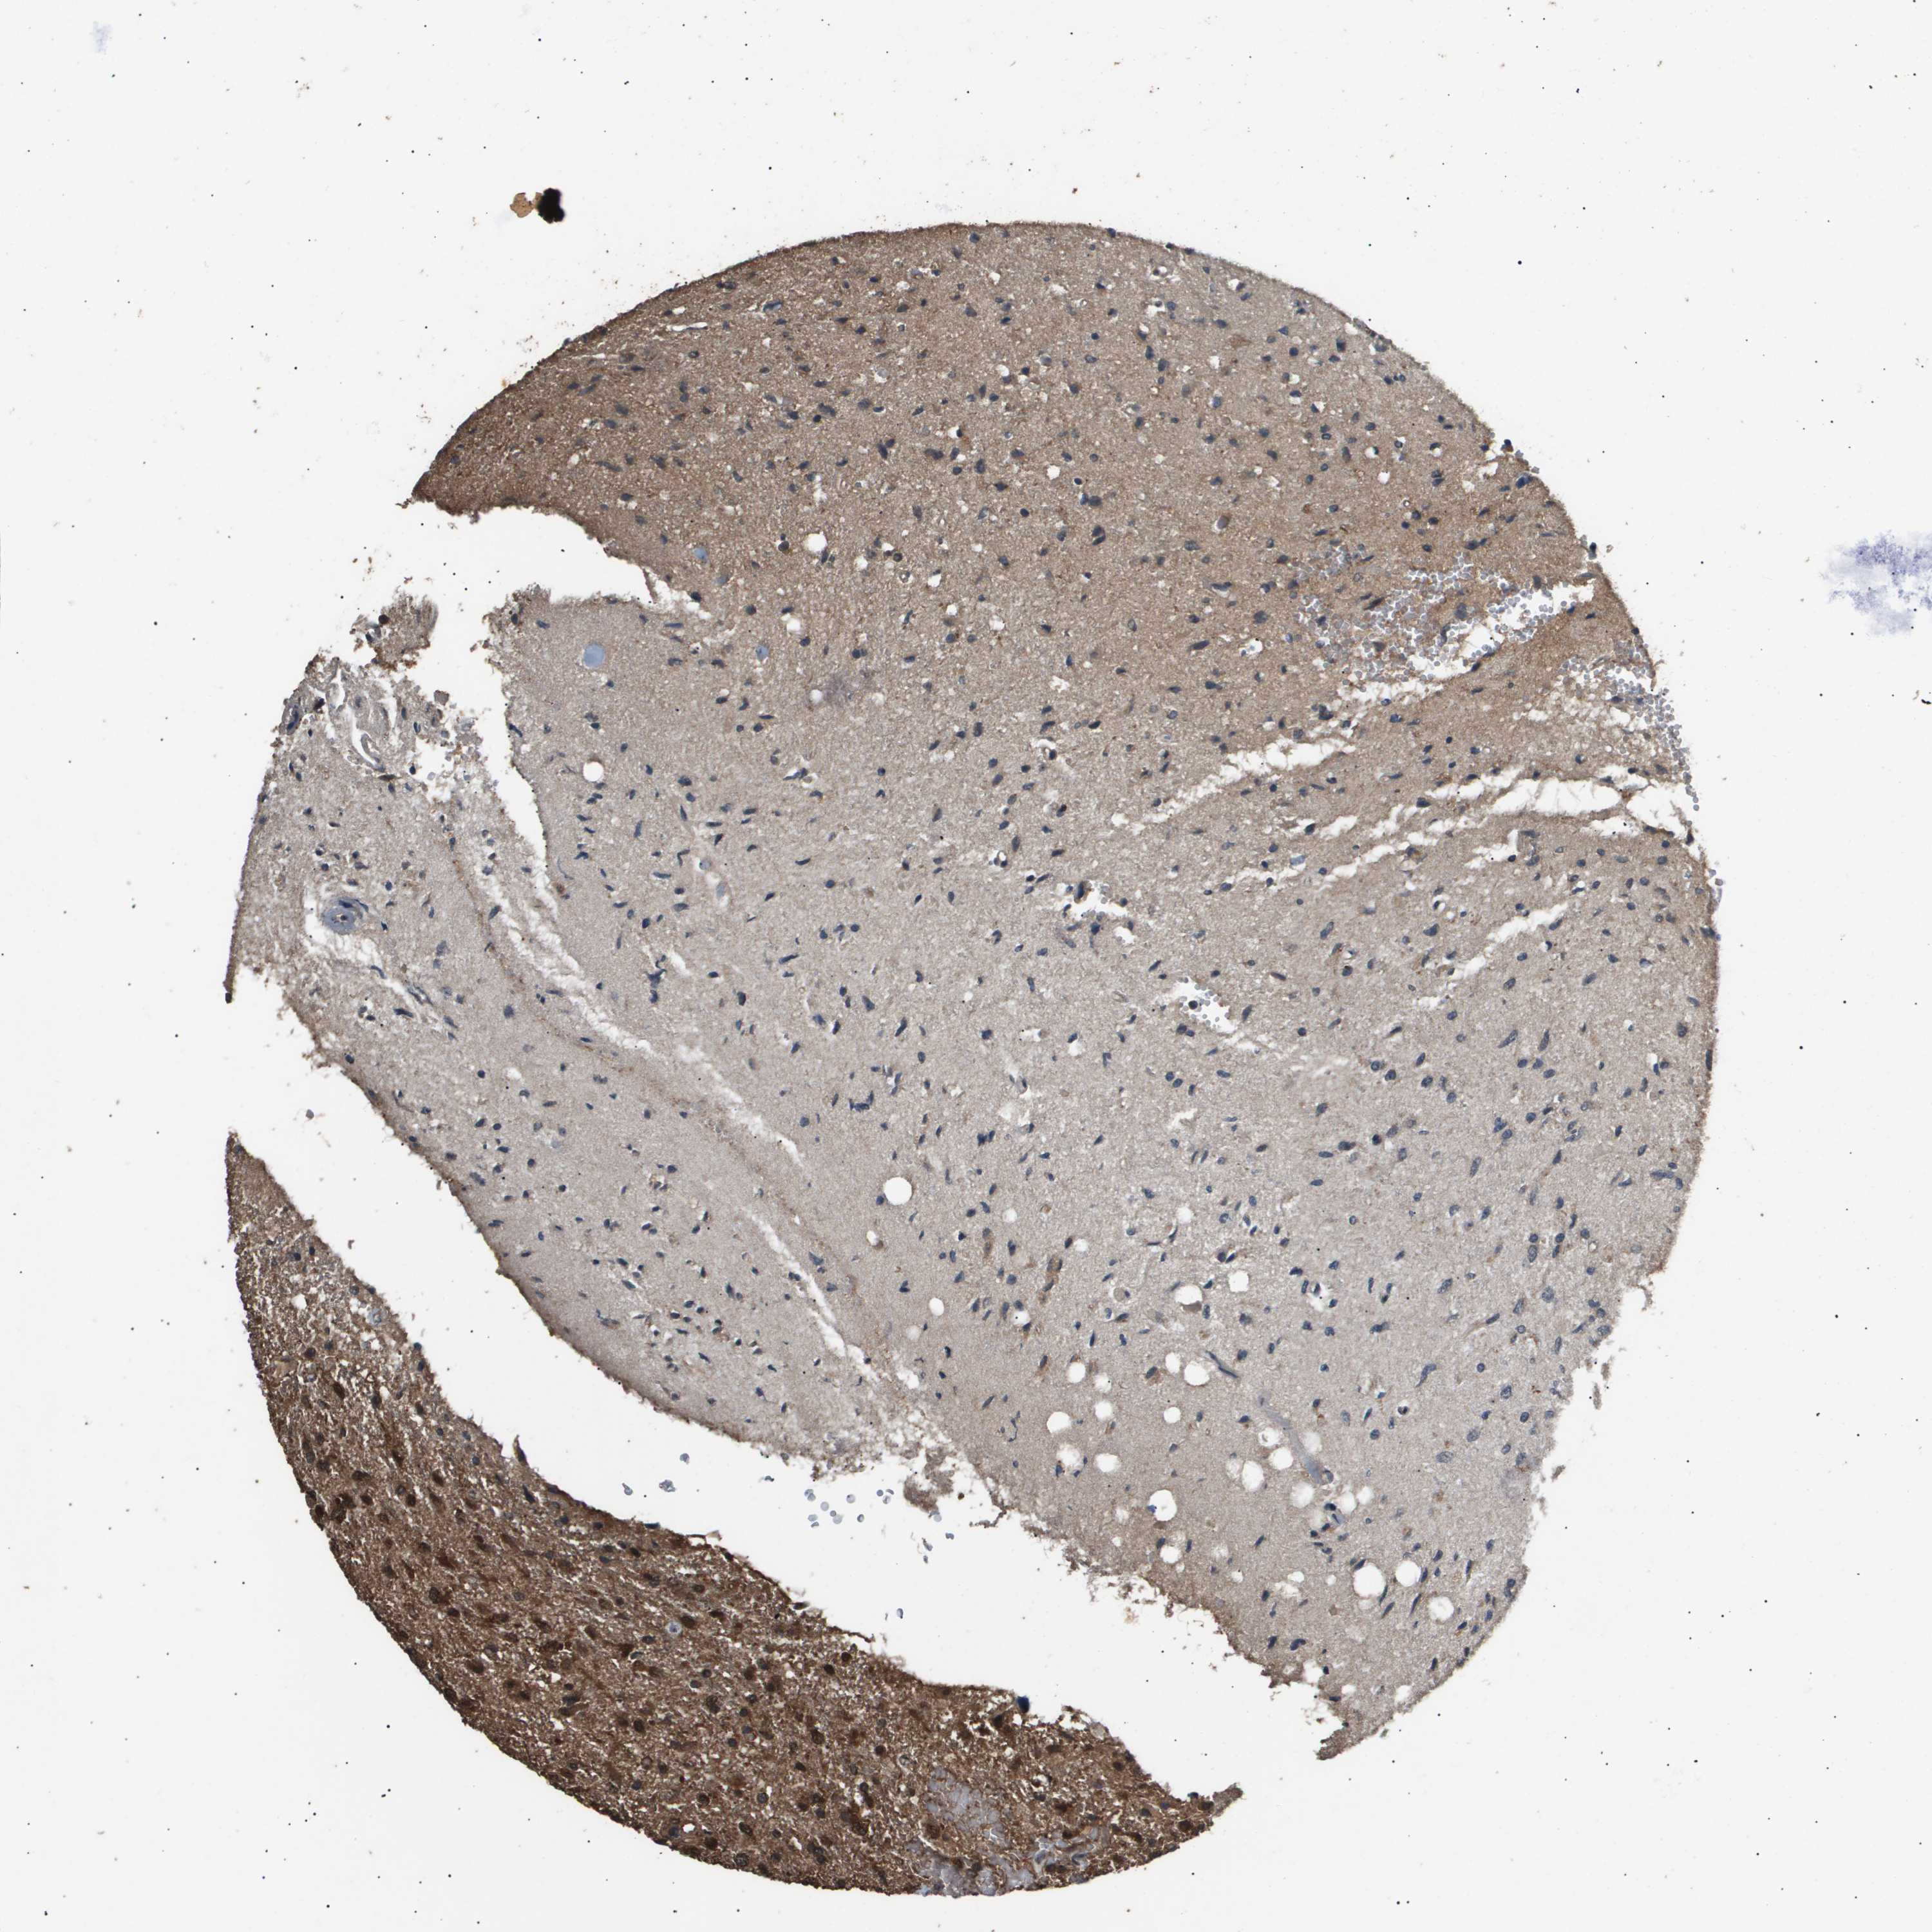

GLIOMA - Protein expressioni

A mouse-over function shows sample information and annotation data. Click on an image to view it in a full screen mode. Samples can be filtered based on level of antibody staining by selecting one or several of the following categories: high, medium, low and not detected. The assay and annotation is described here.

Note that samples used for immunohistochemistry by the Human Protein Atlas do not correspond to samples in the TCGA dataset.

Antibody stainingi

Antibody staining in the annotated cell types in the current human tissue is reported as not detected, low, medium, or high, based on conventional immunohistochemistry profiling in selected tissues. This score is based on the combination of the staining intensity and fraction of stained cells.

Each image is clickable and will lead to virtual microscopy that enables deeper exploration of all samples and also displays staining intensity scores, fraction scores and subcellular localization as well as patient and tissue information for each sample.

Antibody CAB016136

Antibody CAB017773

Staining

High

Medium

Low

Not detected

Intensity

Strong

Moderate

Weak

Negative

Quantity

>75%

75%-25%

<25%

None

Location

Nuclear

Cytoplasmic/membranous

Cytoplasmic/membranous,nuclear

Glioma, malignant, High grade

Glioma, malignant, Low grade